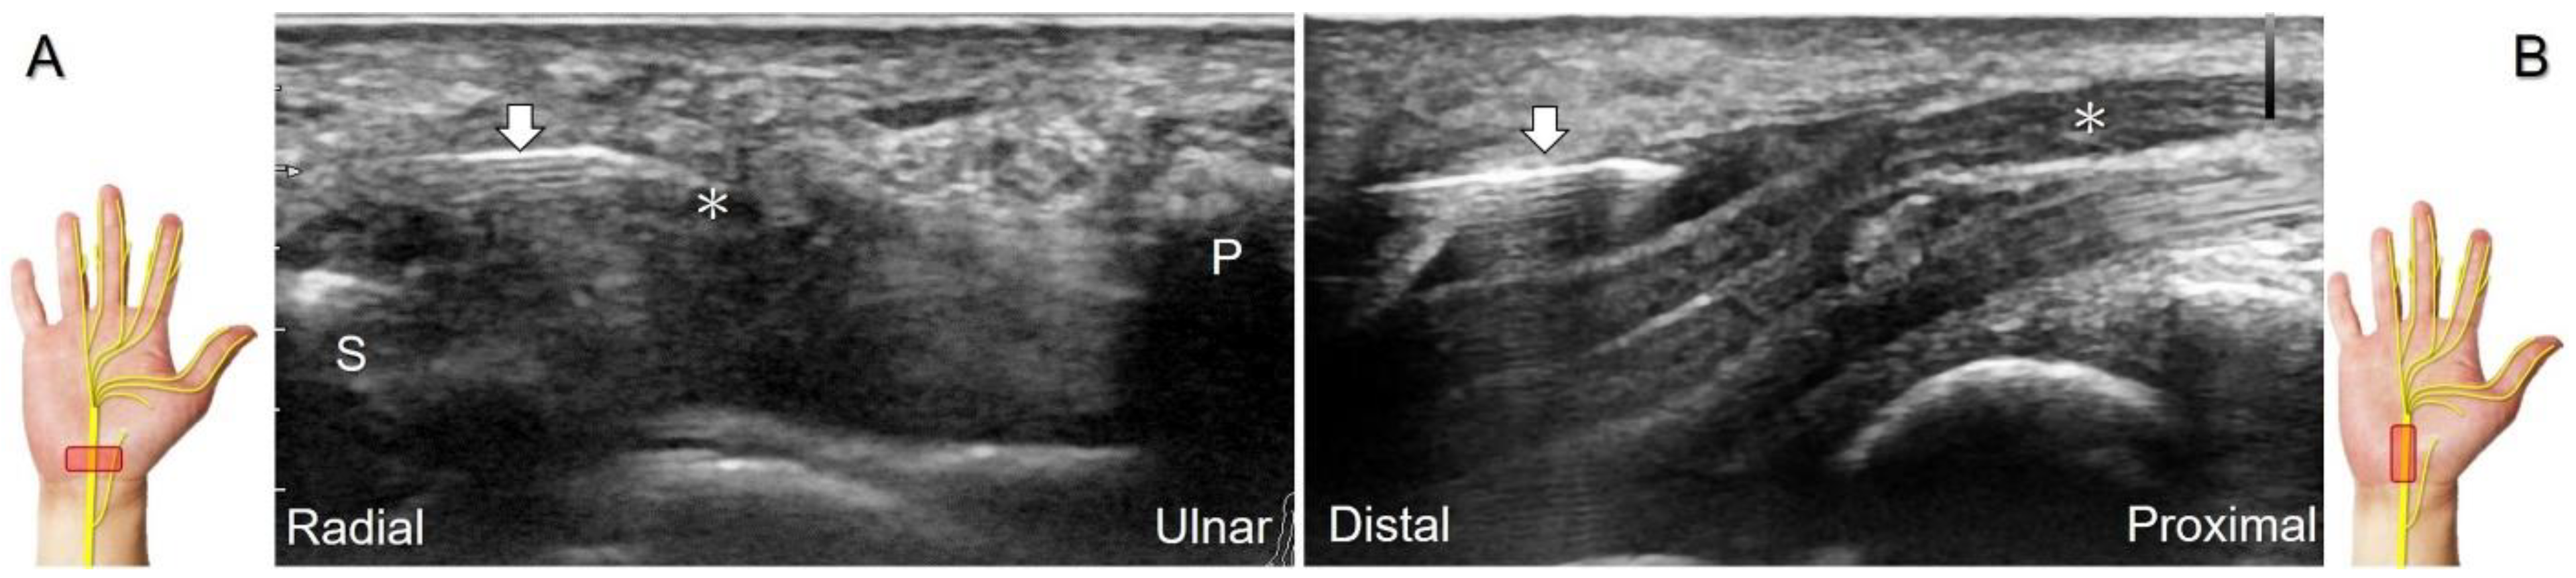

For those receiving surgery such as fixation or debridement of the radial wrist, the nerve can be occasionally injured, resulting in residual numbness, allodynia, dysesthesia, or hypoesthesia (Figure 25).

Figure 25. Sonographic images depict the location of a neuroma of the superficial radial nerve. The normal/proximal segment (A) and the neuroma in short-axis (B) and long-axis (C) views are seen. White arrowhead: superficial radial nerve; black arrowheads: neuroma; APL: abductor pollicis longus tendon; EPB: extensor pollicis brevis tendon; ECRL: extensor carpi radialis longus tendon; C: cephalic vein.